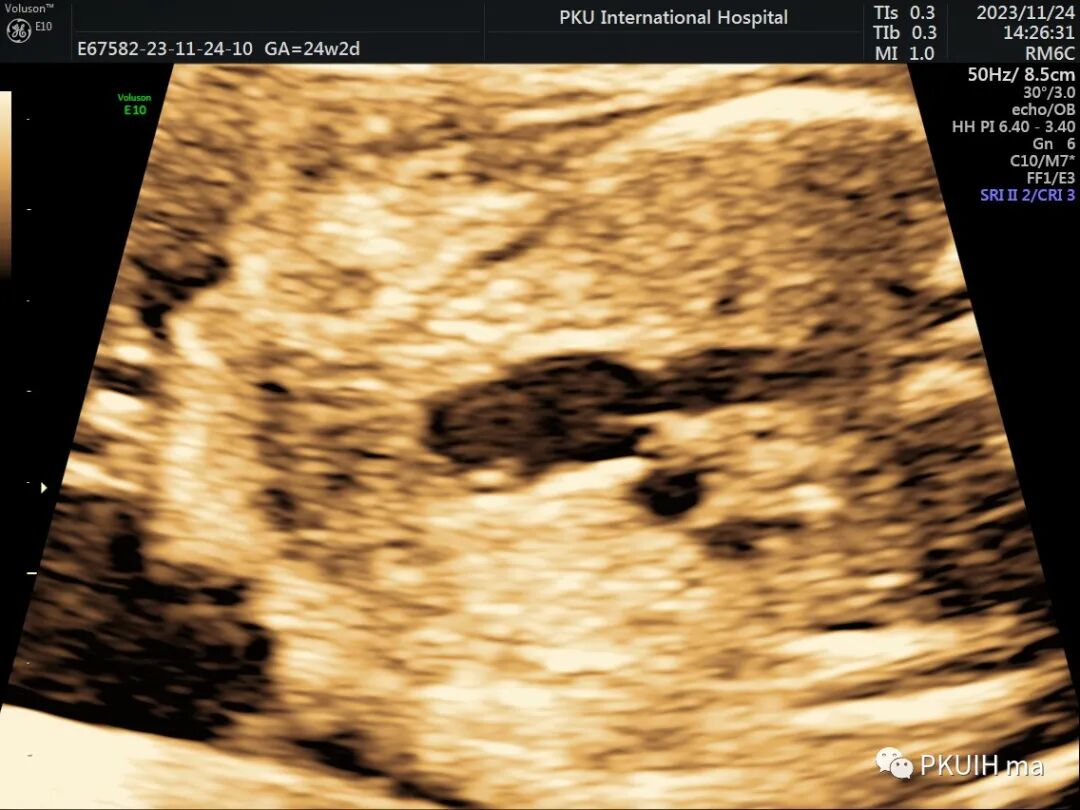

首先我们要通过四腔心切面观察左右心比例。孤立性CoA四腔心切面显示左右心比例失调,左心小右心大(如下图)。当右室与左室横径比值>1.6时提示可能存在CoA。中孕期敏感度较高,晚孕期可出现假阳性。可以通过测量左室内径、二尖瓣环内径及主动脉瓣环内径计算Z值,内径小Z值<–2提示CoA发生风险增高。